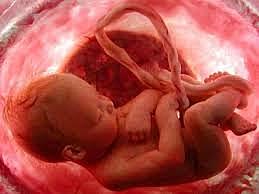

• Semana 9

Semana 9

Genitales externos comienzan a diferenciarse, deglución de líquido amniótico, succión del pulgar, hipófisis produce ACTH y gonadotropina, corteza suprerrenal produce corticoides, válvulas del corazón completas,